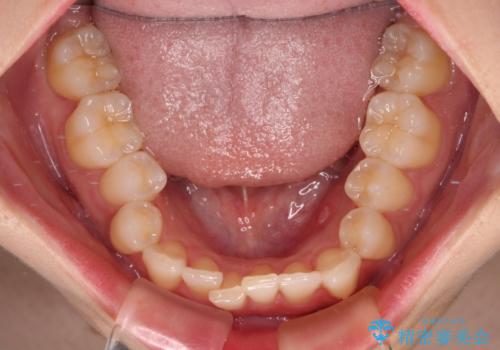

- 前歯のデコボコを気にして来院された患者様です。

全体的にデコボコが多く、特に下の前歯は隠れてしまうほどの状態でした。

左右ともに奥歯の咬み合わせが理想的な位置にあったこともあり、患者様のご希望通り、インビザラインにて矯正治療を行うこととしました。